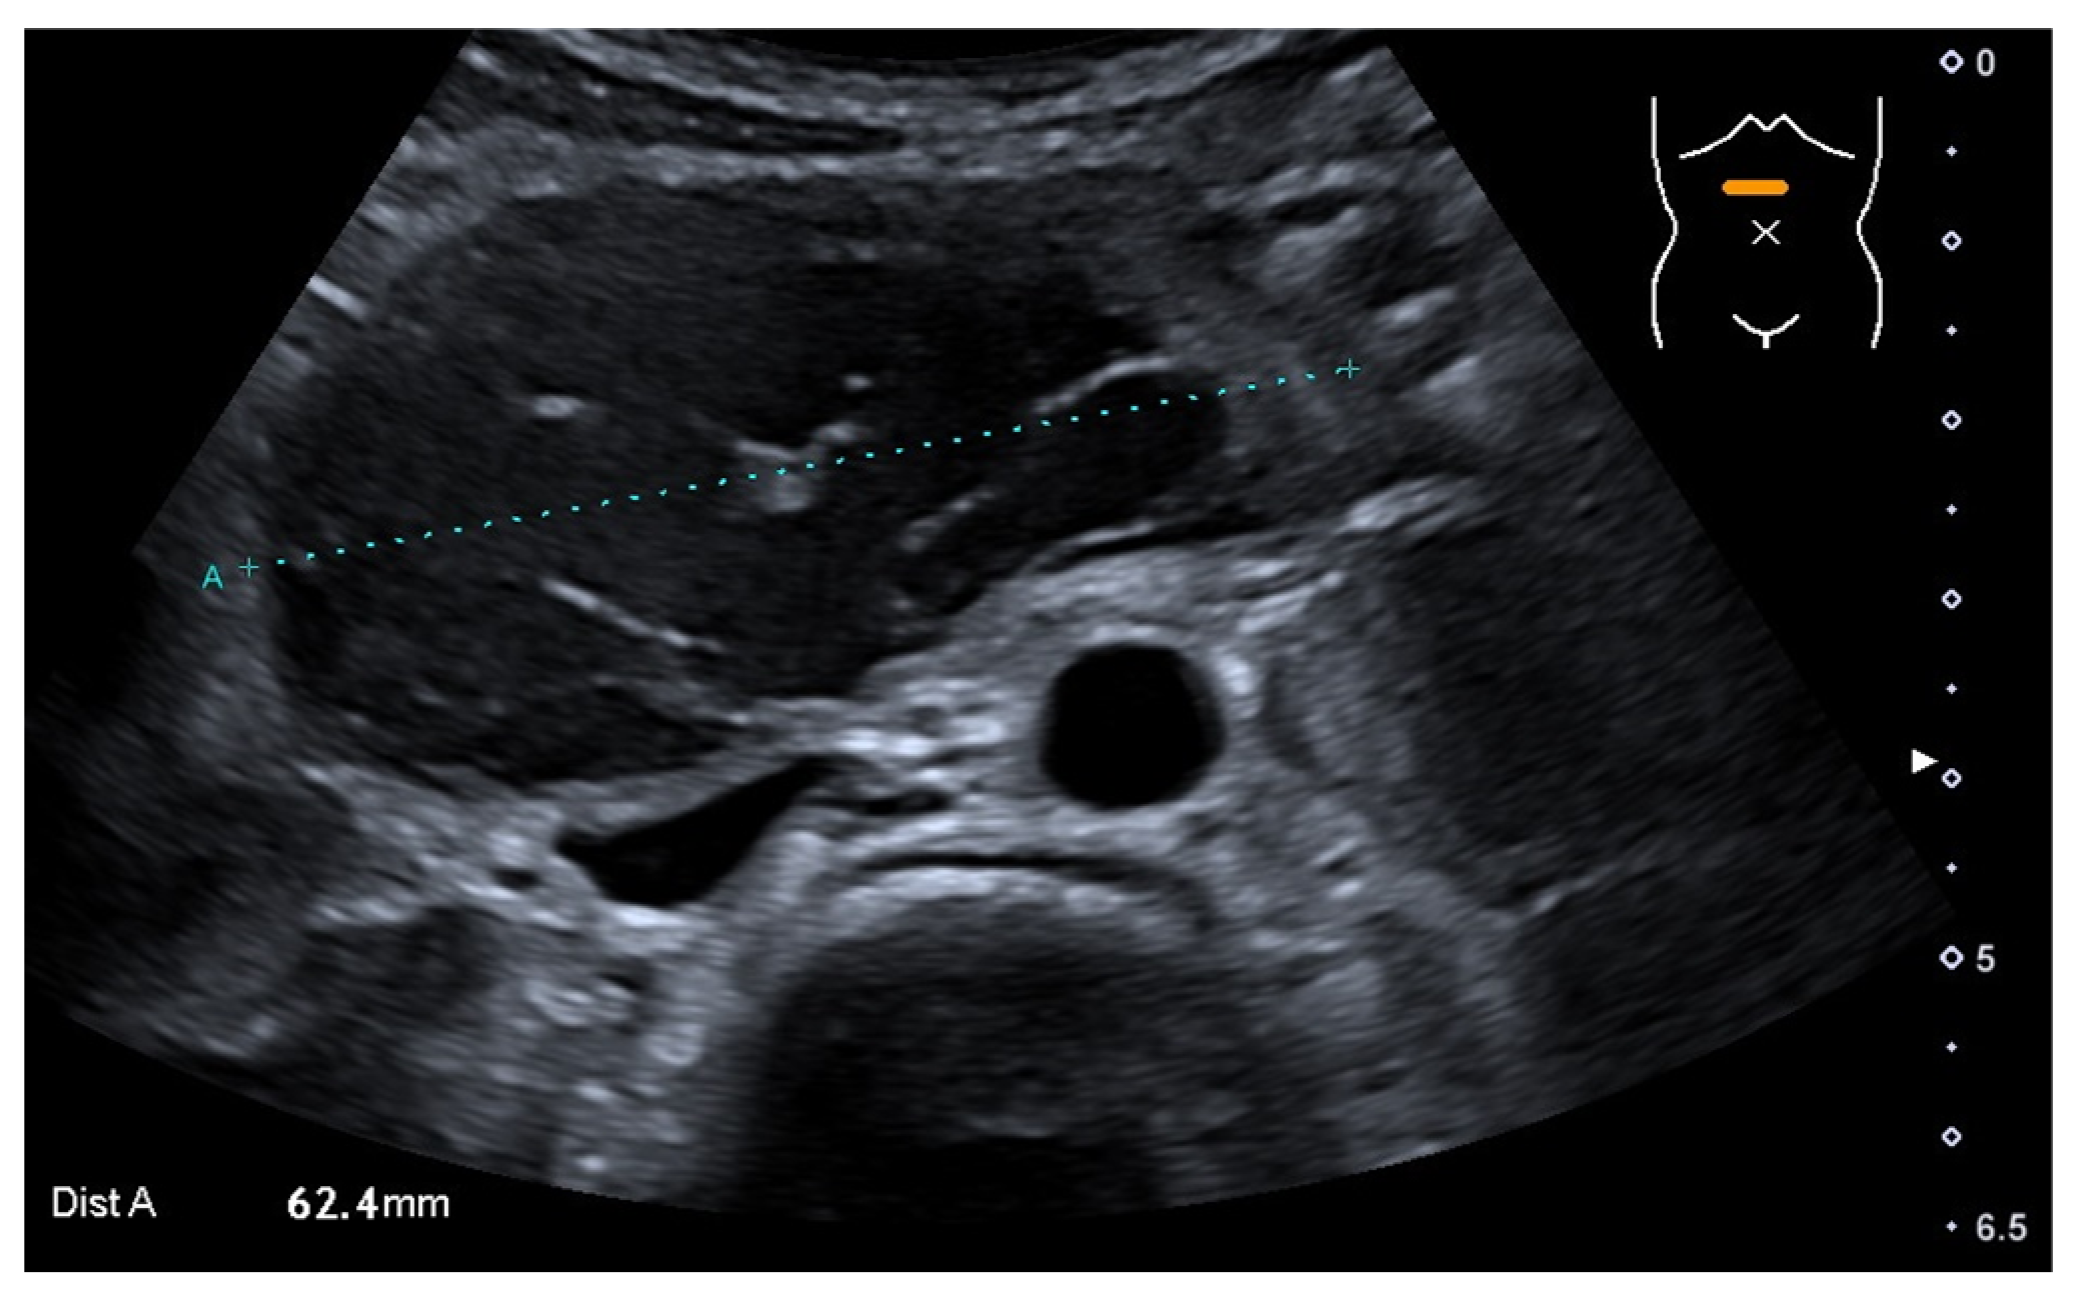

A blood examination, including hemoglobin value (9.2 mmol/L—normal value (nv): 7.4–9.1 mmol/L), platelet count (441 Gpt/L—nv: 150–530 Gpt/L), prothrombin time (94%—nv: 70–130%), partial thromboplastin time (24.1 s—nv: 27–40 s) and the international normalized ratio (1.03—nv: 0.8–1.25) gave no evidence of impaired blood clotting or anemia. Prior to the procedure, no further coagulation diagnostics were available due to the inconspicuous medical and family history of bleeding. The initial ultrasound (Figure 1) examination revealed the suspicion of a large IDH causing a mechanic ileus of the proximal small intestine. The subsequently performed magnetic resonance imaging (MRI, Figure 2) confirmed the suspected diagnosis—a large IDH in the area of the duodenal C with an extent of 62 × 36 × 35 mm that completely compressed the intestinal lumen in the sense of mechanical ileus.

Figure 1.

Initial abdominal ultrasound with intramural hematoma of the duodenum (dotted line), which completely compressed its lumen.